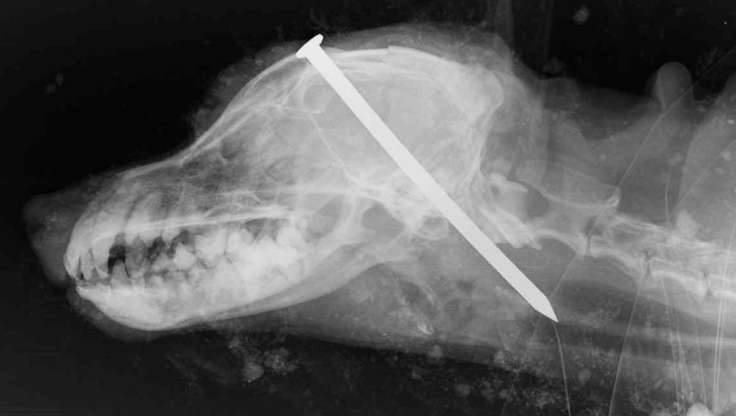

▼前日,英国雷德卡(Redcar)传出一件会让所有爱狗人士都气哭的消息,一名59岁的饲主希思科克(Michael Heathcock)狠心的将自己饲养了16年的老约克夏Scamp用铁钉钉入脑中,发现狗狗没断气,还丢到土中活埋。

▼最令人心疼的是,Scamp被活埋到土中后虽已焉焉一息却尚未断气,一对经过此地的夫妇在听到土堆里传来的狗叫声后,才发现了这间惨绝人寰的悲剧。他们虽已尽快将Scamp送往兽医院接受治疗,但仍无力回天,最终只能替Scamp进行安乐死。治疗Scamp的兽医指出,Scamp的头上至少受到6次重击,这是他行医30年来见过最严重的虐狗事件。